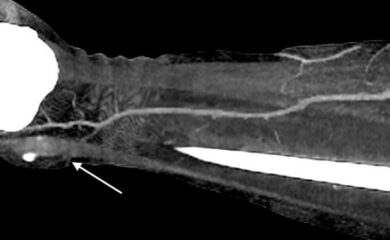

Ефективність передопераційної діагностики з використанням КТ-ангіографії при реконструктивних втручаннях на нижніх кінцівках

Авторы: С. В. Слєсаренко, П. О. Бадюл, С. О. Мунтян, К. С. Слєсаренко, О. О. Ковбаса Статья опубликована в журнале: Клін. хірургія. – 2016. – № …